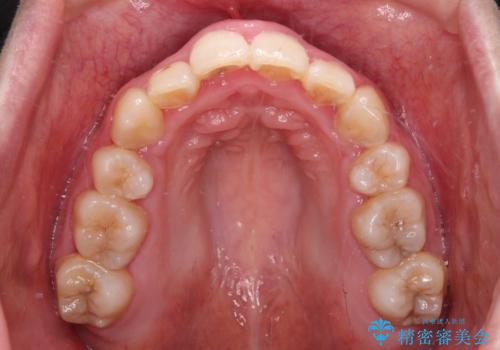

- 骨格的な咬み合わせのズレ、前歯のデコボコとクロスバイトを気にして来院された患者様です。

口元の突出感が若干あり口が閉じにくく、デコボコが強いため、上下左右の小臼歯計4歯を抜歯し、ワイヤー装置による矯正治療を行うこととしました。

治療中に舌の突出癖が改善されず、下顎前歯が著しく前方に突出して反対咬合となってしまう局面がありました。

アンカースクリューを使用しながら舌癖の改善を図り、何とか咬み合わせを改善することができました。